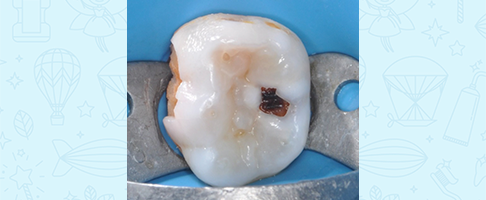

Лечение кариеса, восстановление зуба коронкой

Лечение кариеса молочного зуба, восстановление коронкой и герметизация фиссур с применением закиси азота

Лечение пульпита молочного зуба, восстановление коронкой

Лечение пульпита молочного зуба, восстановление коронкой

Лечение пульпита молочного зуба, восстановление коронкой